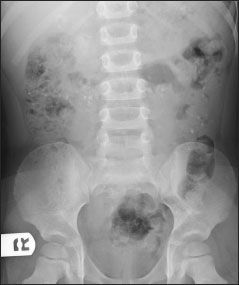

Figure – The multiple round densities visible on this 4-year-old boy’s abdominal radiograph probably represented pebbles that he had ingested. The mother had noticed pebbles in her son’s stool, and laboratory studies revealed iron deficiency. Pica was diagnosed.

In their Photoclinic case of iron deficiency in a 4-year-old boy with pica (CONSULTANT FOR PEDIATRICIANS, March 2009, page 104), Drs Ron Shaoul and David Bader do a commendable job of describing pica and of documenting the child’s iron deficiency (Figure). However, I was surprised that the possibility of lead poisoning was not considered.

In their Photoclinic case of iron deficiency in a 4-year-old boy with pica (CONSULTANT FOR PEDIATRICIANS, March 2009, page 104), Drs Ron Shaoul and David Bader do a commendable job of describing pica and of documenting the child’s iron deficiency (Figure). However, I was surprised that the possibility of lead poisoning was not considered. Perhaps lead poisoning is not a common problem in Israel, but pica of this degree should lead pediatricians in the United States to have serious concerns about plumbism.